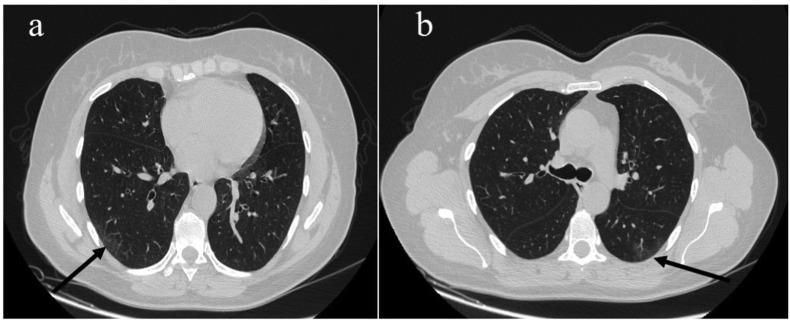

Typical CT findings of COVID-19 pneumonia in patients presenting with repetitive negative RT-PCR.

Multiple polymerase chain reaction (RT-PCR) is considered the gold standard diagnostic investigation for severe acute respiratory syndrome coronavirus 2 (SARS-CoV-2) that causes coronavirus disease 2019 (COVID-19). However, false negative multiple polymerase chain reaction (RT-PCR) results can be diagnostically challenging. We report three patients with history of fever and different clinical signs. During the height of the pandemic in Italy (March to May 2020), these patients underwent chest computed tomography (CT) scans that showed lung alterations typical of COVID-19 with multiple negative RT-PCR tests and positive serology for SARS-CoV-2. Two of the three patients showed residual pneumonia on CT after the onset of the first clinical signs. One patient presented with diarrhoea without respiratory symptoms. These cases suggest that in the COVID-19 pandemic period, to provide an earlier specific treatment in patients with positive serology, a chest CT scan can be useful in those presenting with a fever or a history of fever associated with persistent mild respiratory symptoms or with abdominal complaints despite repeated negative RT-PCR results.